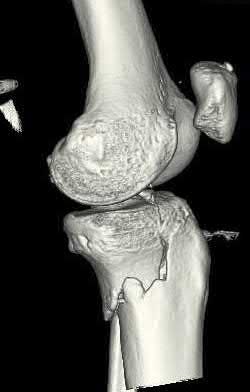

A 38-year-old male suffers the injury shown in Figure A. During operative fixation, free osteoarticular fragments are encountered and reconstruction of these pieces is attempted. Postoperatively, which of the following will have the most beneficial effect on the healing potential of the surviving chondrocytes within these reconstructed articular segments?

Figure A demonstrates a comminuted tibial plateau fracture with significant intra-articular involvement. Basic science evidence has demonstrated that post-operative gentle compressive loading may have a positive impact on articular cartilage healing; however, excessive shear loading may be detrimental.

Irrgang et al provide guidelines for rehabilitation following surgical management of articular cartilage lesions of the knee. They state that after articular cartilage repair, exercises to enhance muscle function must be done in a manner which minimizes shear loading of the joint surfaces in the area of the lesion. The authors also discuss the benefits of gentle compressive loading and motion of the joint, and its positive effects on chondrocyte nutrition.

Furthermore, they recommend a period of protected weight bearing as often being necessary, and that this should be followed by progressive loading of the joint.